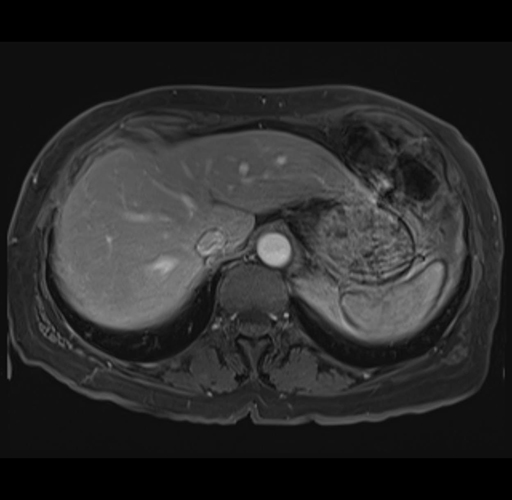

MRI T1

Imaging analysis